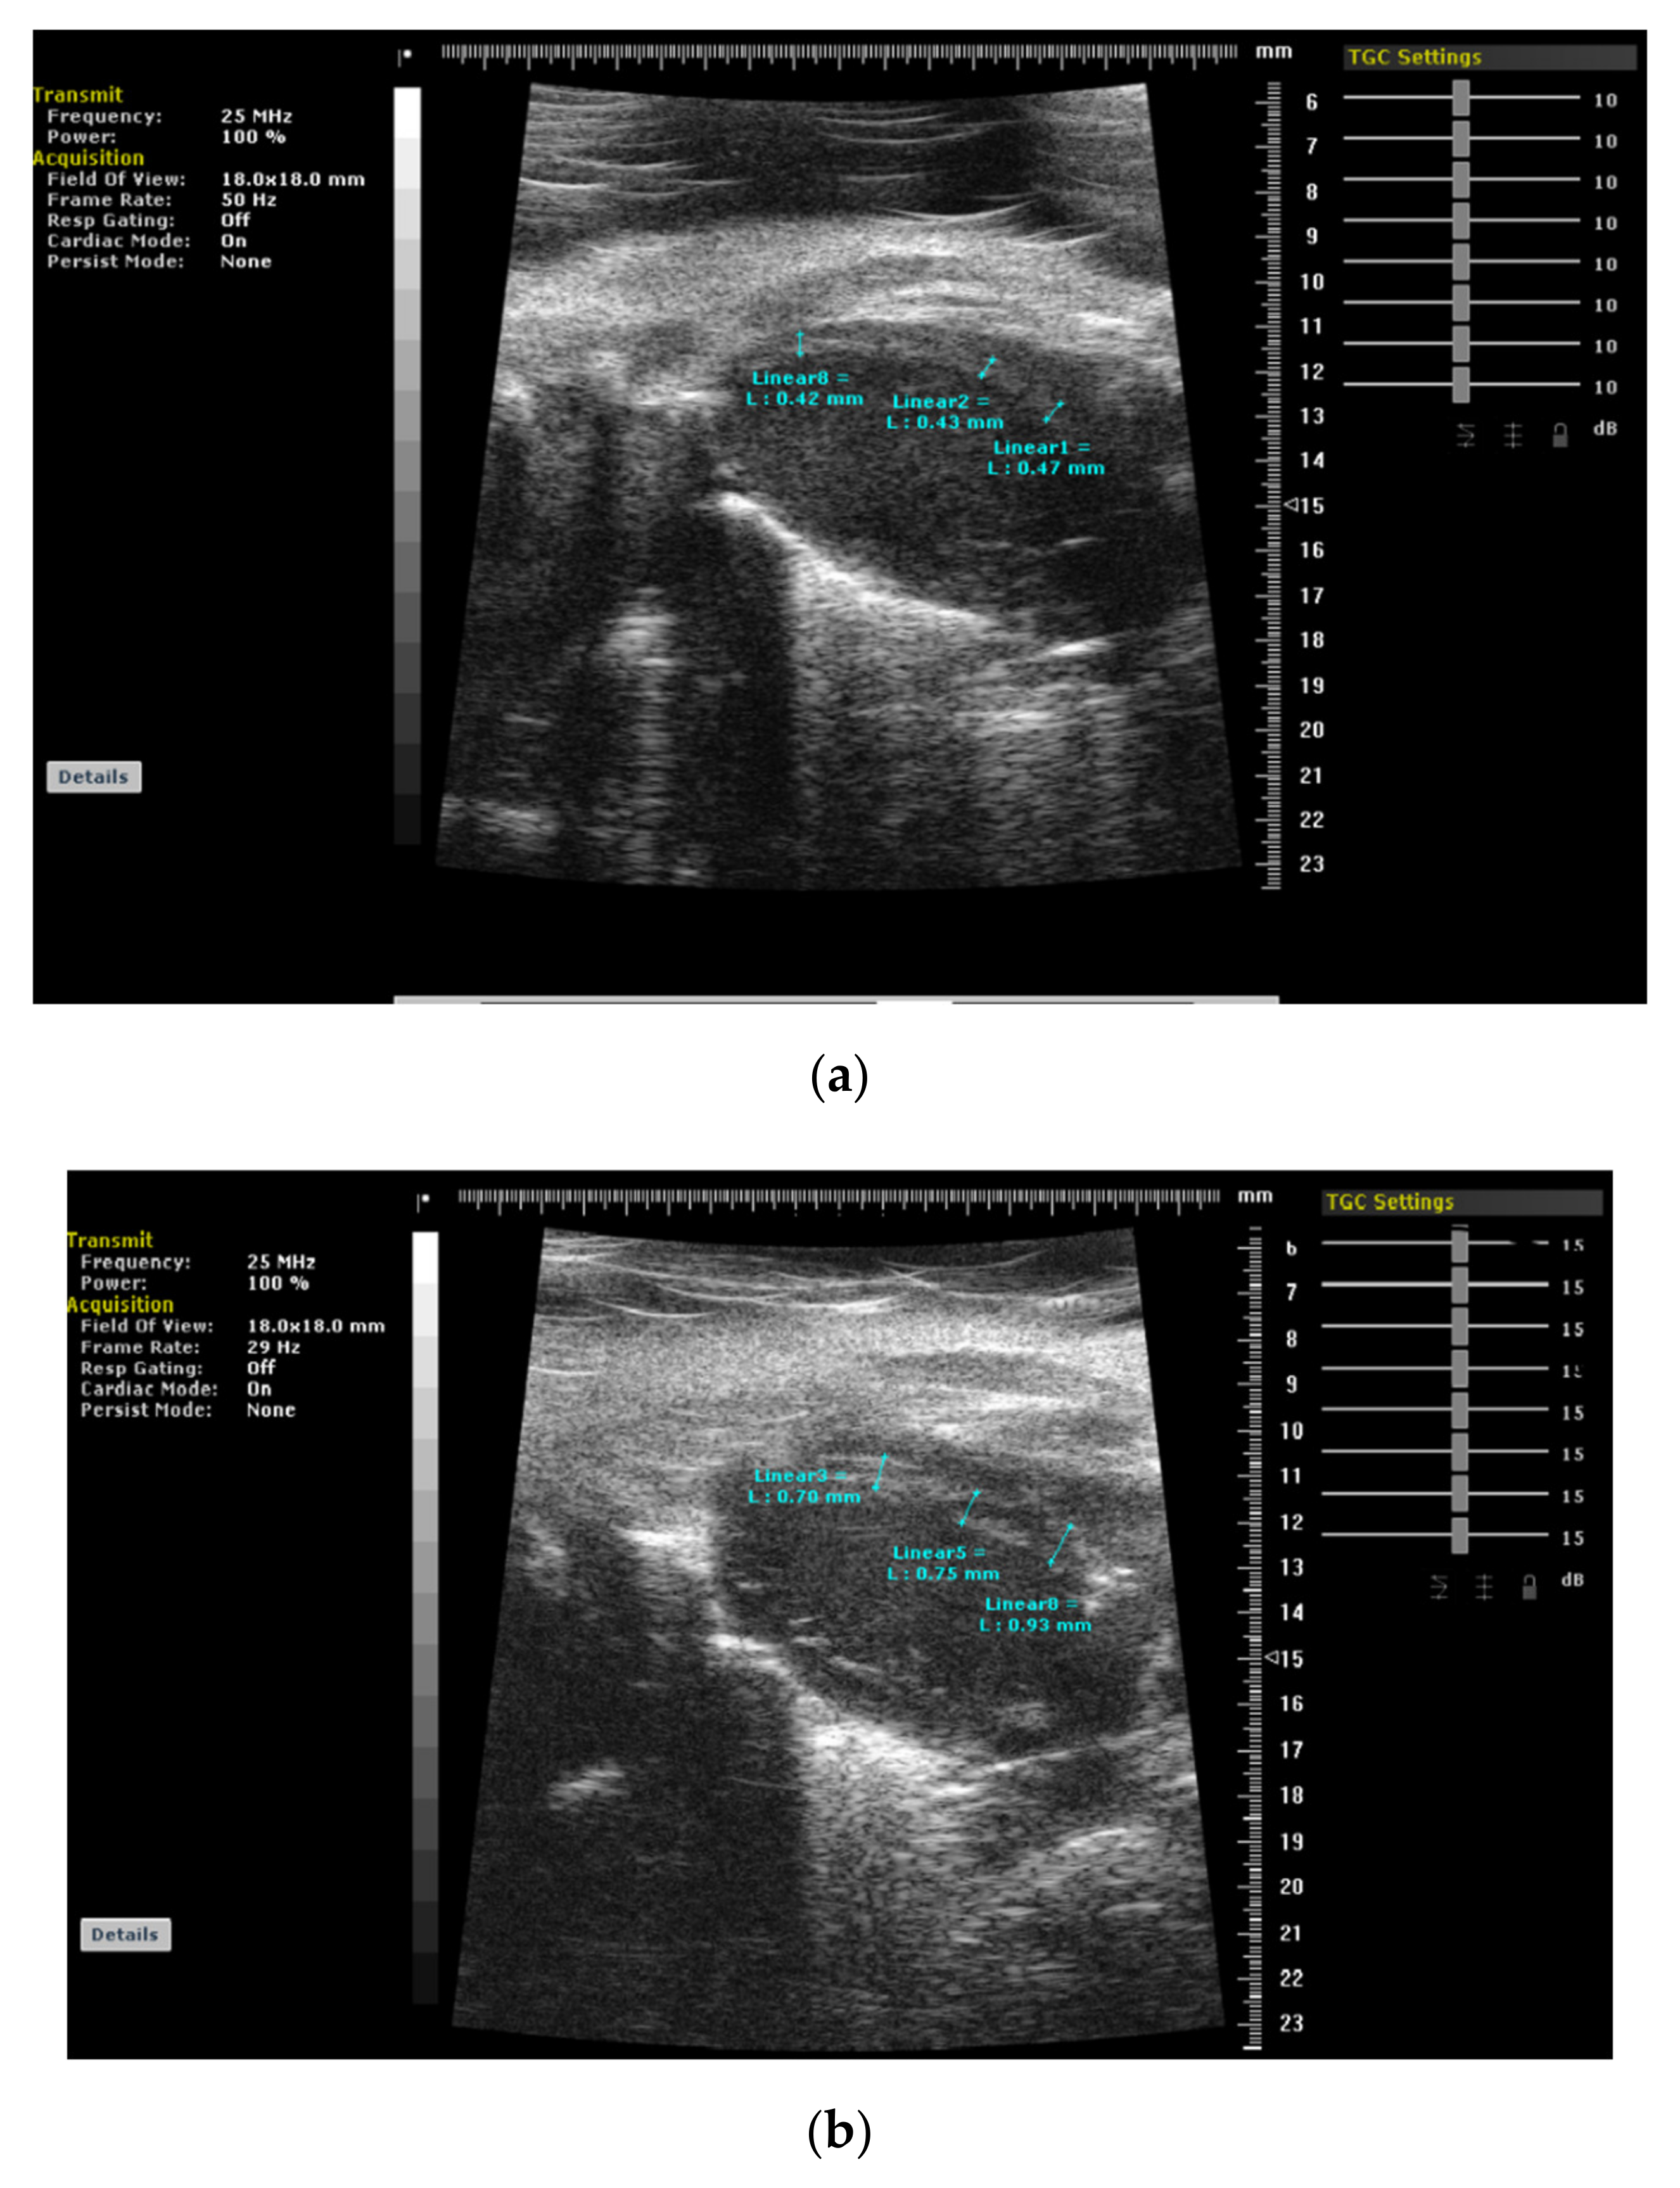

3. BSH and Animal Validation Studies

- Yalçin, F.; Kucukler, N.; Cingolani, O.; Mbiyangandu, B.; Sorensen, L.; Pinherio, A.; Abraham, M.R.; Abraham, T.P. Evolution of ventricular hypertrophy and myocardial mechanics in physiologic and pathologic hypertrophy. J. Appl. Physiol. 2019, 126, 354–362. [Google Scholar] [CrossRef]

- Yalçin, F.; Kucukler, N.; Cingolani, O.; Mbiyangandu, B.; Sorensen, L.; Pinherio, A.; Abraham, M.R.; Abraham, T.P. Intracavitary gradient in mice with early regional remodeling at the compensatory hyperactive stage prior to left ventricular tissue dysfunction. J. Am. Coll. Cardiol. 2020, 75, 1585. [Google Scholar] [CrossRef]